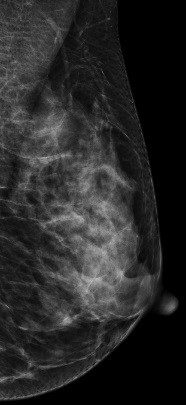

DBT图像:

常规2D图像在MLO位上象限发现靠近胸大肌处见一不对称团块影,CC位上并没有发现明显肿块影,右乳外象限局部结构较乱,DBT图像左乳外上象限清晰可见一不规则肿块影,呈分叶状,与周边腺体组织界限欠清

影像诊断:

左乳外上肿物--考虑良性可能性大BI-RADS 3级